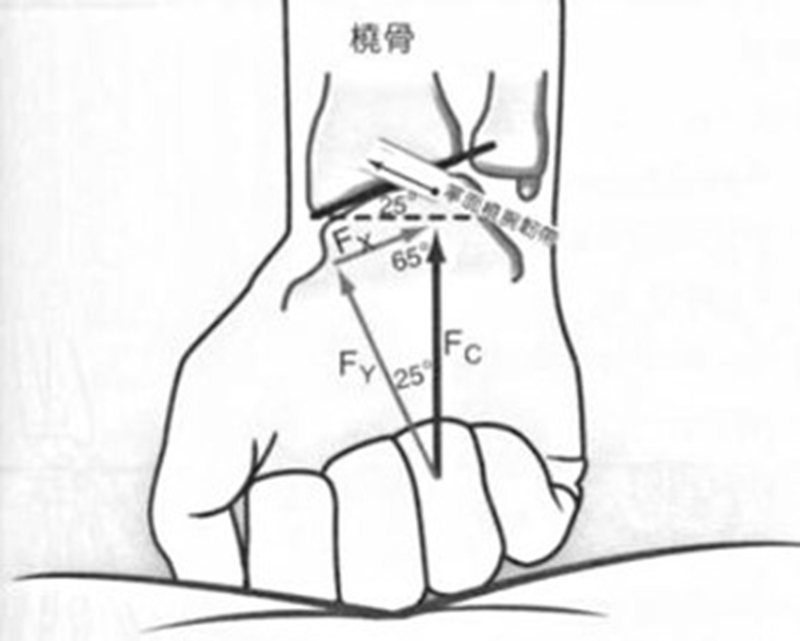

TFCC的功能

TFCC主要具有以下3个功能:远端桡尺关节(DRUJ)的主要稳定结构;稳定尺侧的腕骨;将尺侧腕骨所受的压力转移至尺骨远端。

TFCC损伤机制

典型受伤机制为前臂旋前、腕关节过伸位时腕尺侧受到直接撞击或牵拉。多在以下场景受伤:网球、高尔夫球、羽毛球等运动者手腕尺侧受力和快速扭转活动;车祸中司机手握方向盘腕部受到旋转牵张暴力;突然摔倒时用手撑地;提重物不慎或手腕用力不当时扭伤等。